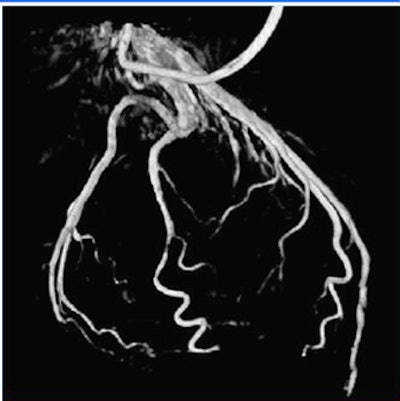

![]() |

| Volume rendering at 68% RR created with automated phase selection and motion compensation. |